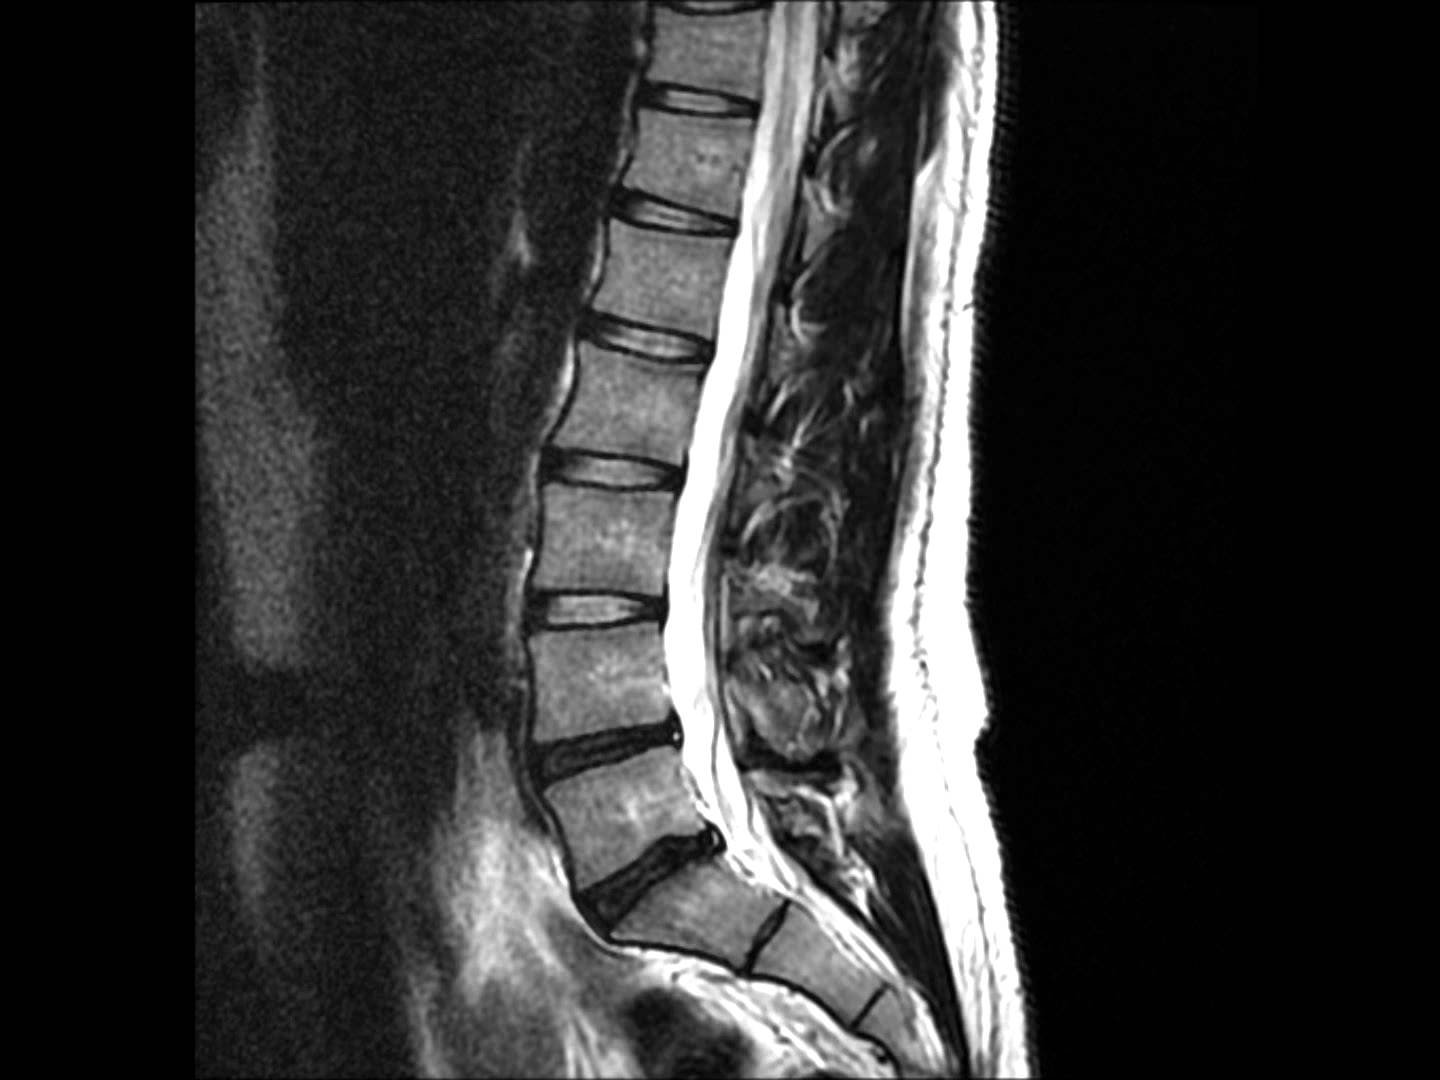

Hình cộng hưởng từ (MRI):